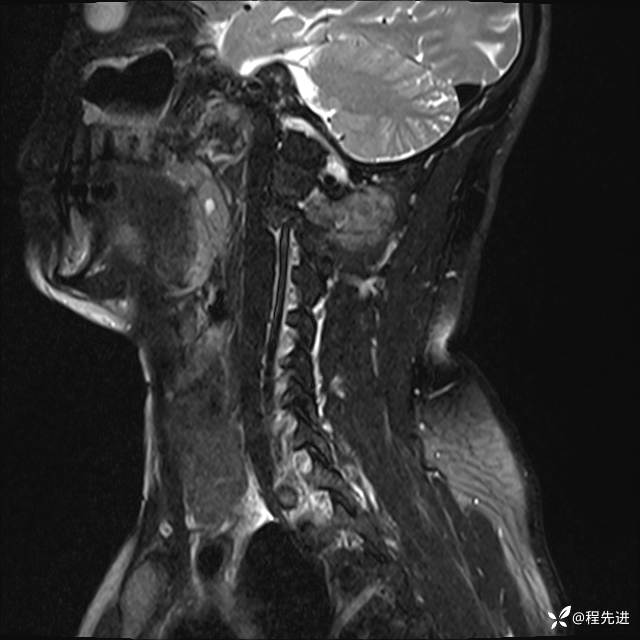

MRI平扫+增强:

T1:

T1增强: